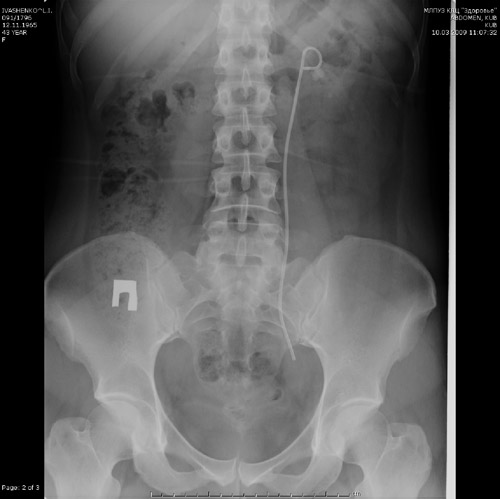

Медицинские технологии: Установка стента